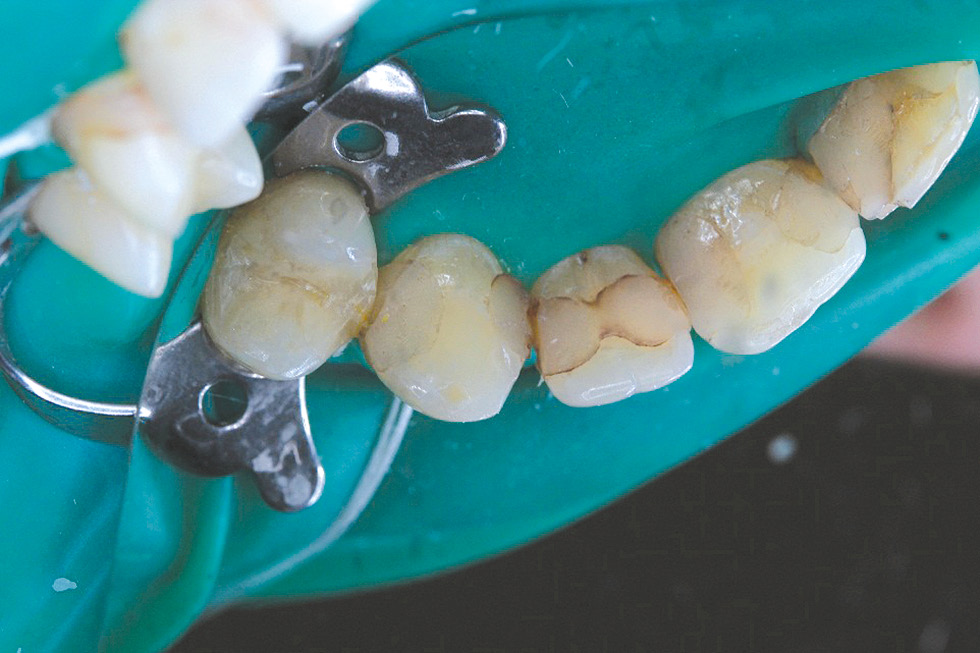

Data of an objective study: mouth opening - in full. The bite is orthognathic. Tooth 1.3: composite restoration on the vestibular and medial surfaces with a pronounced violation of the marginal fit (Fig. 8), the same on the distal and palatal surfaces (Fig. 9). In the cervical region 1.3, there is a slit-like defect of hard tissues with a change in color and softening of the dentin.

Diagnosis: secondary caries 1.3 (dentine caries) K02.1.

Treatment plan: removal of failed restoration 1.3, direct composite restoration 1.3. Given the significant defects in the hard tissues of the vestibular surface 1.3, it seems important to achieve the maximum possible degree of adhesion of the composite material to the hard tissues of the tooth, therefore, a combination of the adhesive system OptiBond Universal (Kerr) and the composite material OptiBond Universal (Kerr) with the effect of polychromy was used.

Treatment was carried out: under infiltration anesthesia Sol. Articaini–1 ml under water-air cooling, failed 1.3 restorations were removed, the vestibular surface was prepared for the manufacture of a direct composite restoration (Fig. 10). Enamel 1.3 was selectively etched, the OptiBond Universal adhesive system (Kerr) was applied, and direct restoration was performed using the OptiShade nanohybrid universal composite (Kerr) (Fig. 11, 12).